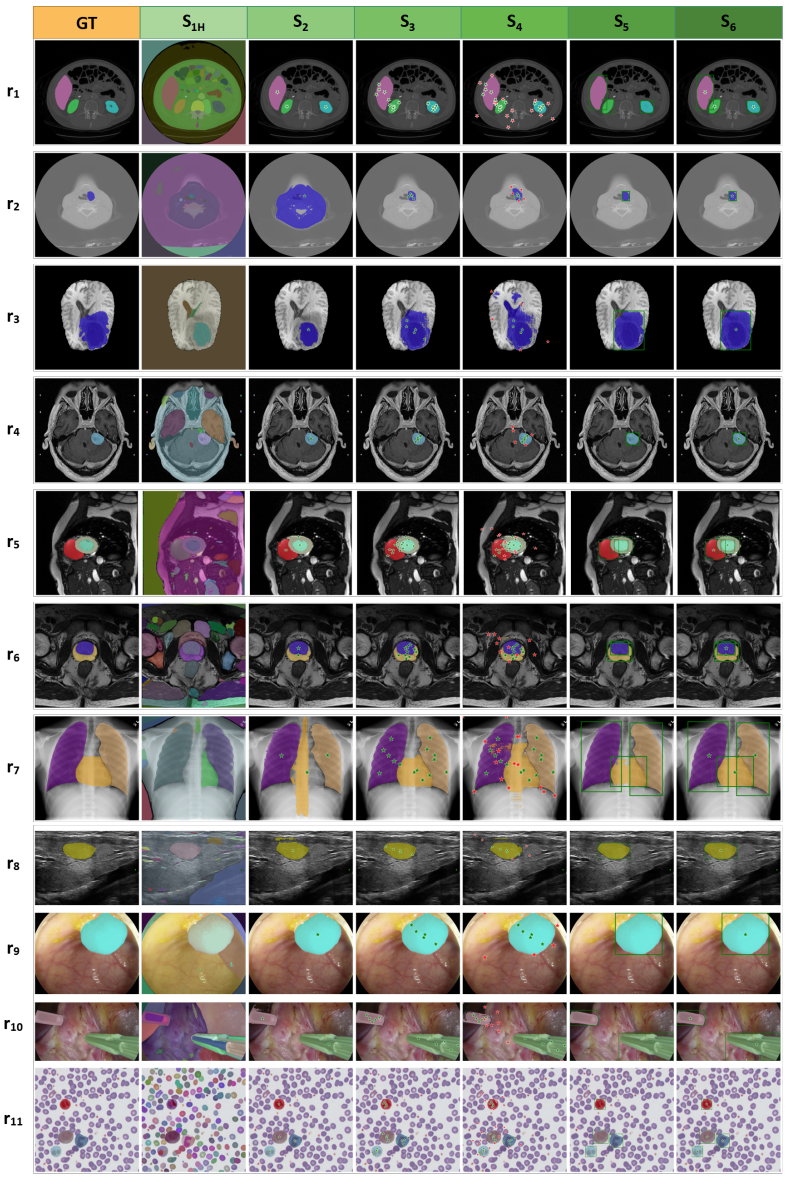

- 在Prompt模式下,加入更多前景点可显著提高SAM的分割结果。但医学影像中的前景和背景很容易混淆,随机加入负样本点可能会引起分割性能下降。此外,方框提示(S5)包含丰富的物体位置信息。因此,在我们的研究中,方框提示在大多数医学分割任务中比点提示表现好。在目前的研究中,混合策略(同时加入点提示和方框提示)的性能没有明显提升。这可能与SAM对混合提示的编码能力有关。图7和图8展示了SAM在各种测试策略下的可视化结果。

图7 典型的SAM良好案例